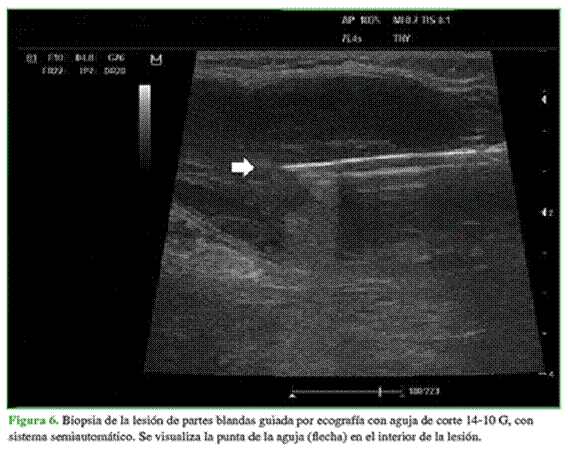

Posteriormente y como se trataba de una única lesión, el Comité de Tumores decide realizar una biopsia guiada por ecografía (Figura 6). El estudio de anatomía patológica informa una neoplasia mesenquimatosa maligna, de células pequeñas y azules, compatible con rabdomiosarcoma. La inmunomarcación arroja el siguiente resultado: 1.Vimentina: Positivo, 2. Desmina: Positivo, 3. S100: Negativo, 4. MYOD1: Positivo, 5. Ki67: Proliferación del 60%, 6. P53: 40% de células positivas.